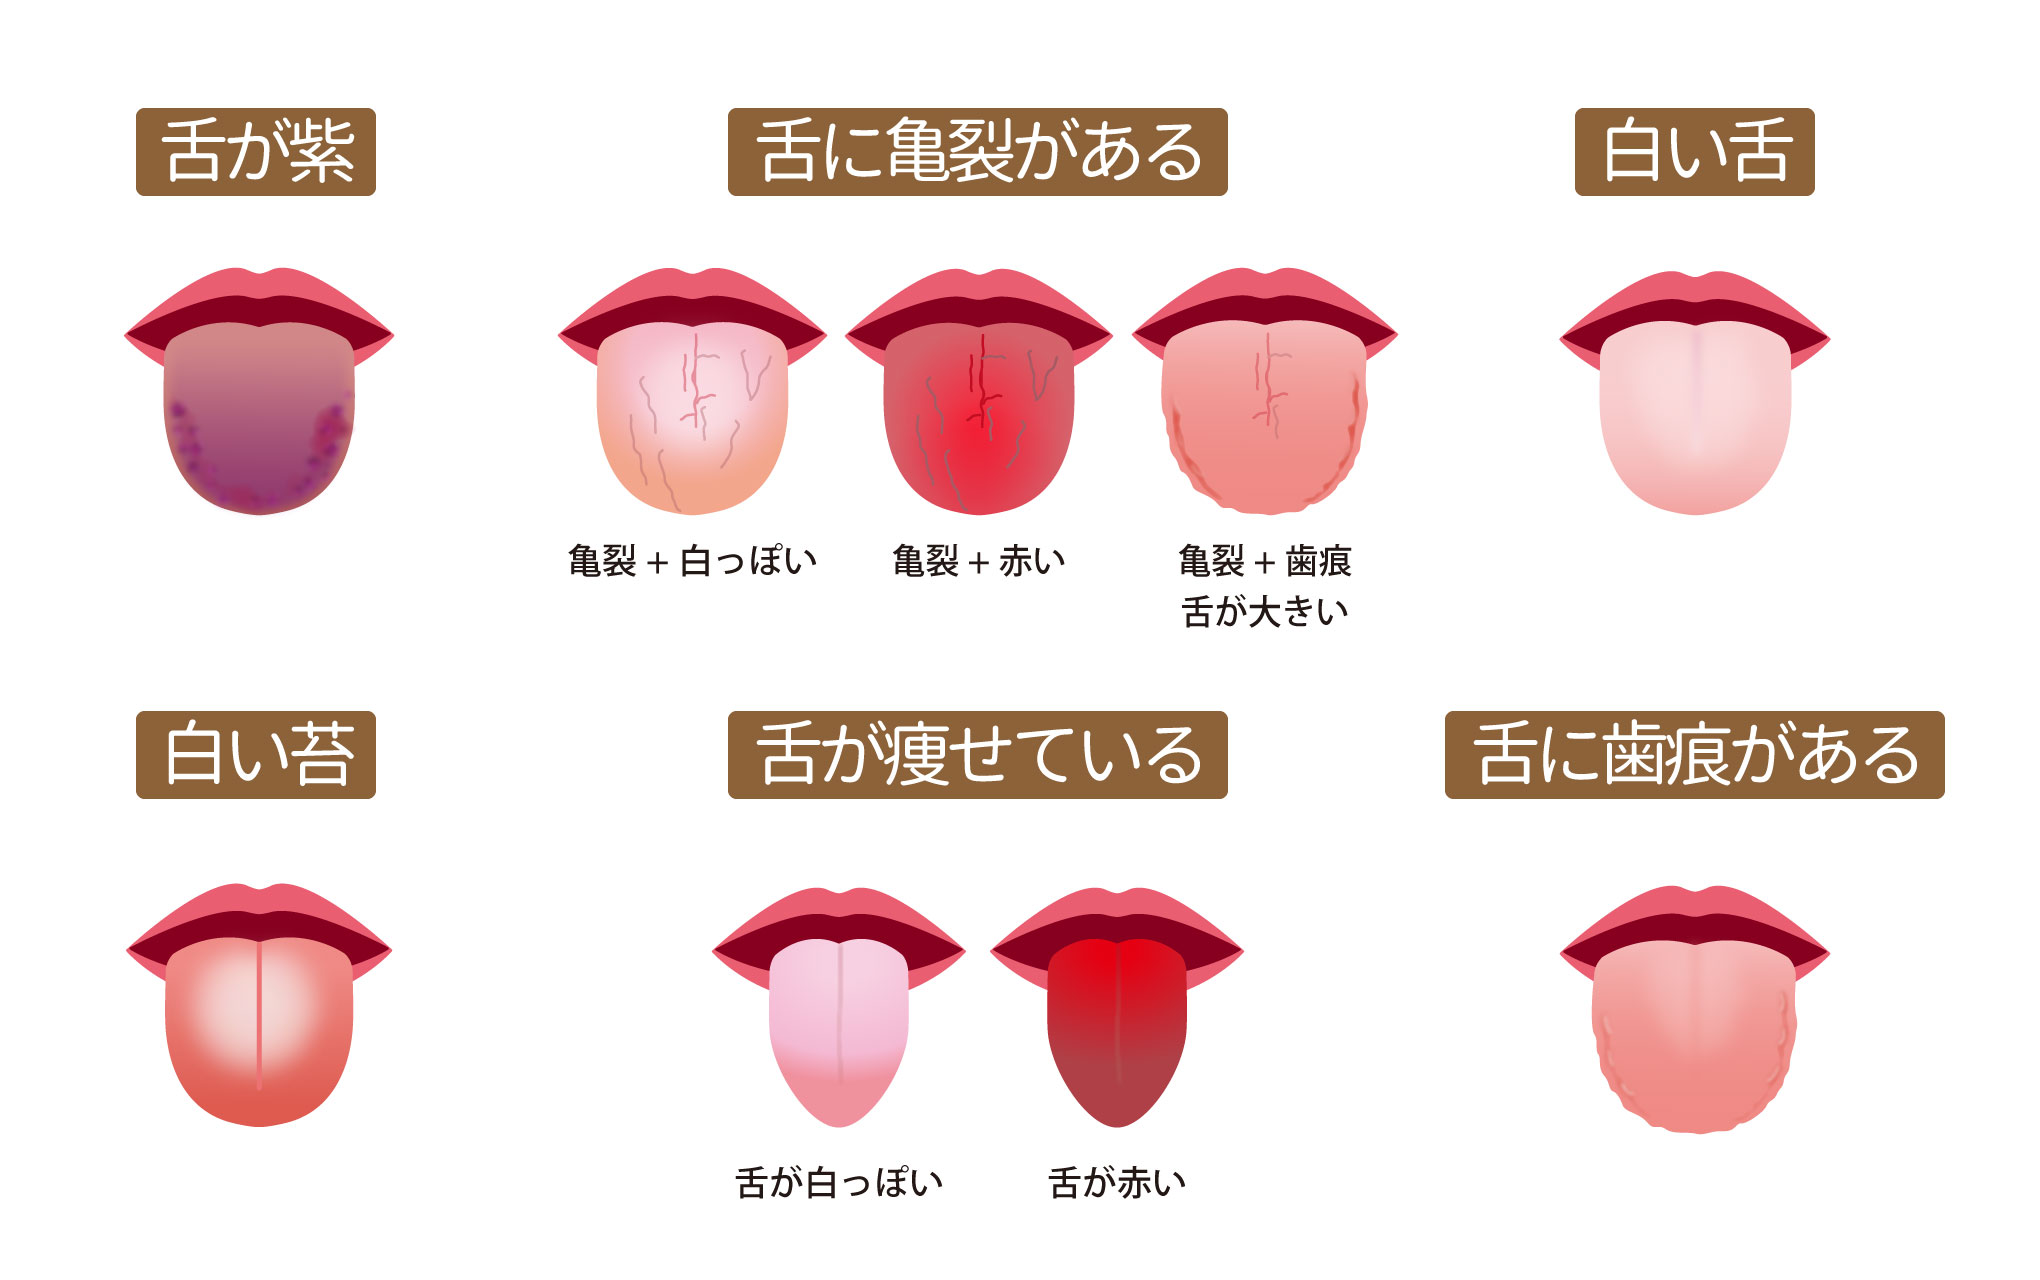

舌にひび割れがある」ときの体質・体調 - 漢方ライフ- 漢方を始めると、暮らしが変わる。

白い、ガタガタ、ひび割れ 。“舌”でわかる体調不良のサインとは?田中友也さん 季節の養生法からだにいいこと。

舌のサイン 院長ブログ八尾市のオカモト鍼灸整骨院。

舌診~毎日鏡の前で健康チェックをしたくなる舌の状態を解説 祥泉針灸整骨院。

舌が割れて溝ができているタイプの疲れ症状 養命酒製造株式会社。

病気サイン?舌がひび割れる4つの原因。溝状舌・ドライマウスはどう治す?病院は何科?Medicalook メディカルック。